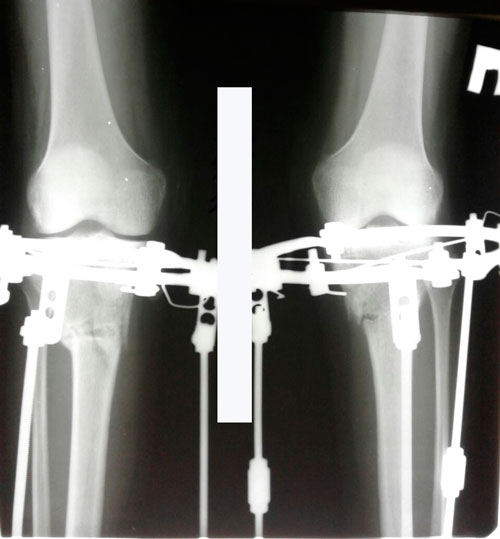

В процессе круток.

IMG-20170726-WA0032.jpg